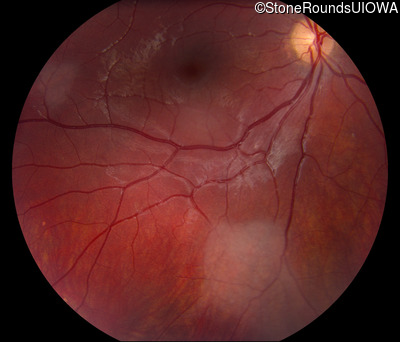

Fundus Photography - Right - 20/20 -1 sc

Exemplar

Fundus Photography - Left - 20/20 -1 sc